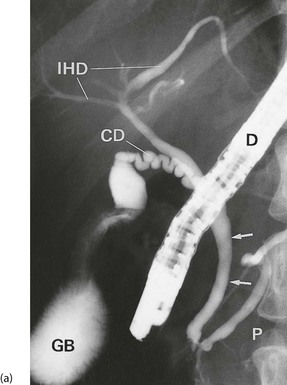

Investigating the biliary duct system: See Figure 20.5.

Fig. 20.5 Investigation of the biliary duct system

(a) Normal ERCP showing duodenoscope D in the second part of the duodenum. Contrast has been injected first into the pancreatic duct P and then into the common bile duct (arrowed). Note also the cystic duct CD, gall bladder GB and intrahepatic bile ducts IHD.